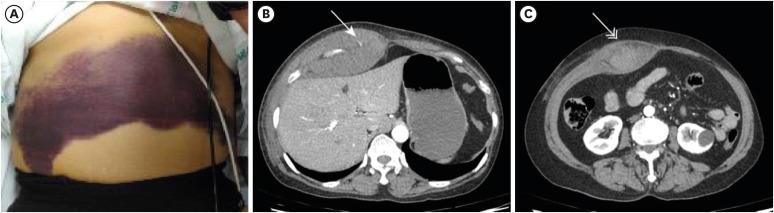

The use of neoadjuvant chemotherapy in older patients is increasing. However, chemotherapy should be administered considering the medical comorbidities of the patients and the toxicity of chemotherapeutic agents. Here, we present a case of abdominal wall hematoma with spontaneous inferior epigastric artery injury caused by coughing in a 70-year-old woman who was treated with neoadjuvant chemotherapy. Abdominal computed tomography demonstrated an abdominal wall hematoma with active bleeding. However, angiography with selective embolization of the right inferior epigastric artery and the right internal mammary artery was performed successfully. Scheduled chemotherapy was discontinued over concerns of rebleeding and breast-conserving surgery was performed. When deciding on chemotherapy for older patients, attention should be paid to the various complications.

老年患者新辅助化疗的应用正在增加。然而,化疗的实施应考虑患者的合并症以及化疗药物的毒性。在此,我们报告一例70岁接受新辅助化疗的女性患者,因咳嗽导致腹壁血肿伴自发性腹壁下动脉损伤。腹部计算机断层扫描显示腹壁血肿伴活动性出血。然而,成功地进行了选择性栓塞右腹壁下动脉和右乳内动脉的血管造影。出于再出血的担忧,预定的化疗被中止,并进行了保乳手术。在为老年患者决定化疗方案时,应注意各种并发症。